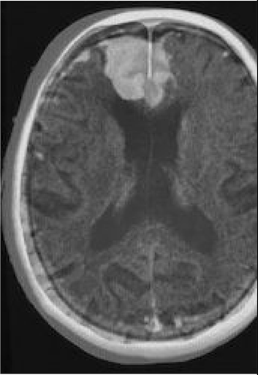

Table 6 Fused image output.

From: Multimodal medical image fusion combining saliency perception and generative adversarial network

Final output